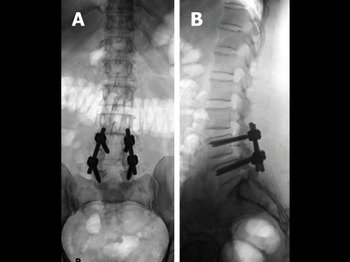

Vary from medical (conservative) treatment along with physio and postural correction to nerve/root blocks (for blocking the affected nerve to give pain relief) to surgical decompression as a last resort (only in 5 pc cases), depending on the severity of the problem

Anti-osteoporoticdrugs/injectionss/ sprays, physical therapy, surgical procedure to relieve pain like vertebroplasty and kyphoplasty, in-house bone density checkup.